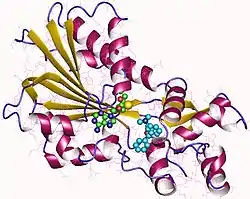

The crystallographic structure (three-dimensional structure) of human HNMT protein was first described in 2001 as a 33kDa monomeric protein consisting of two structural domains.[12][13][11]

The first domain, called the "MTase domain", contains the active site where methylation occurs. It has a classic fold found in many other methyltransferases, and consists of a seven-stranded beta-sheet surrounded by three helices on each side. This domain binds to its cofactor, S-adenosyl-L-methionine (SAM-e), which provides the methyl group for Nτ-methylation reactions.[12][13]

The second domain, called the "substrate binding domain", interacts with histamine, contributing to its binding to the enzyme molecule. This domain is connected to the MTase domain and forms a separate region. It includes an antiparallel beta sheet along with additional alpha helices and 310 helices.[12][13]